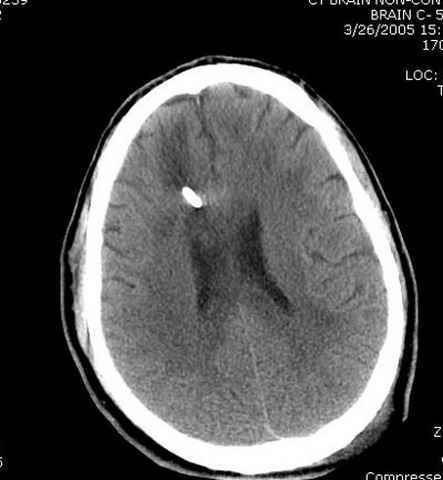

Наблюдается службой травмы и нейрохирургии (ICP) Increased Intracranial Pressure by ventricular cateter

больной без сознания, со слов нейрохирурга, наблюдается положительная динамика в нейрохирургическом статусе.